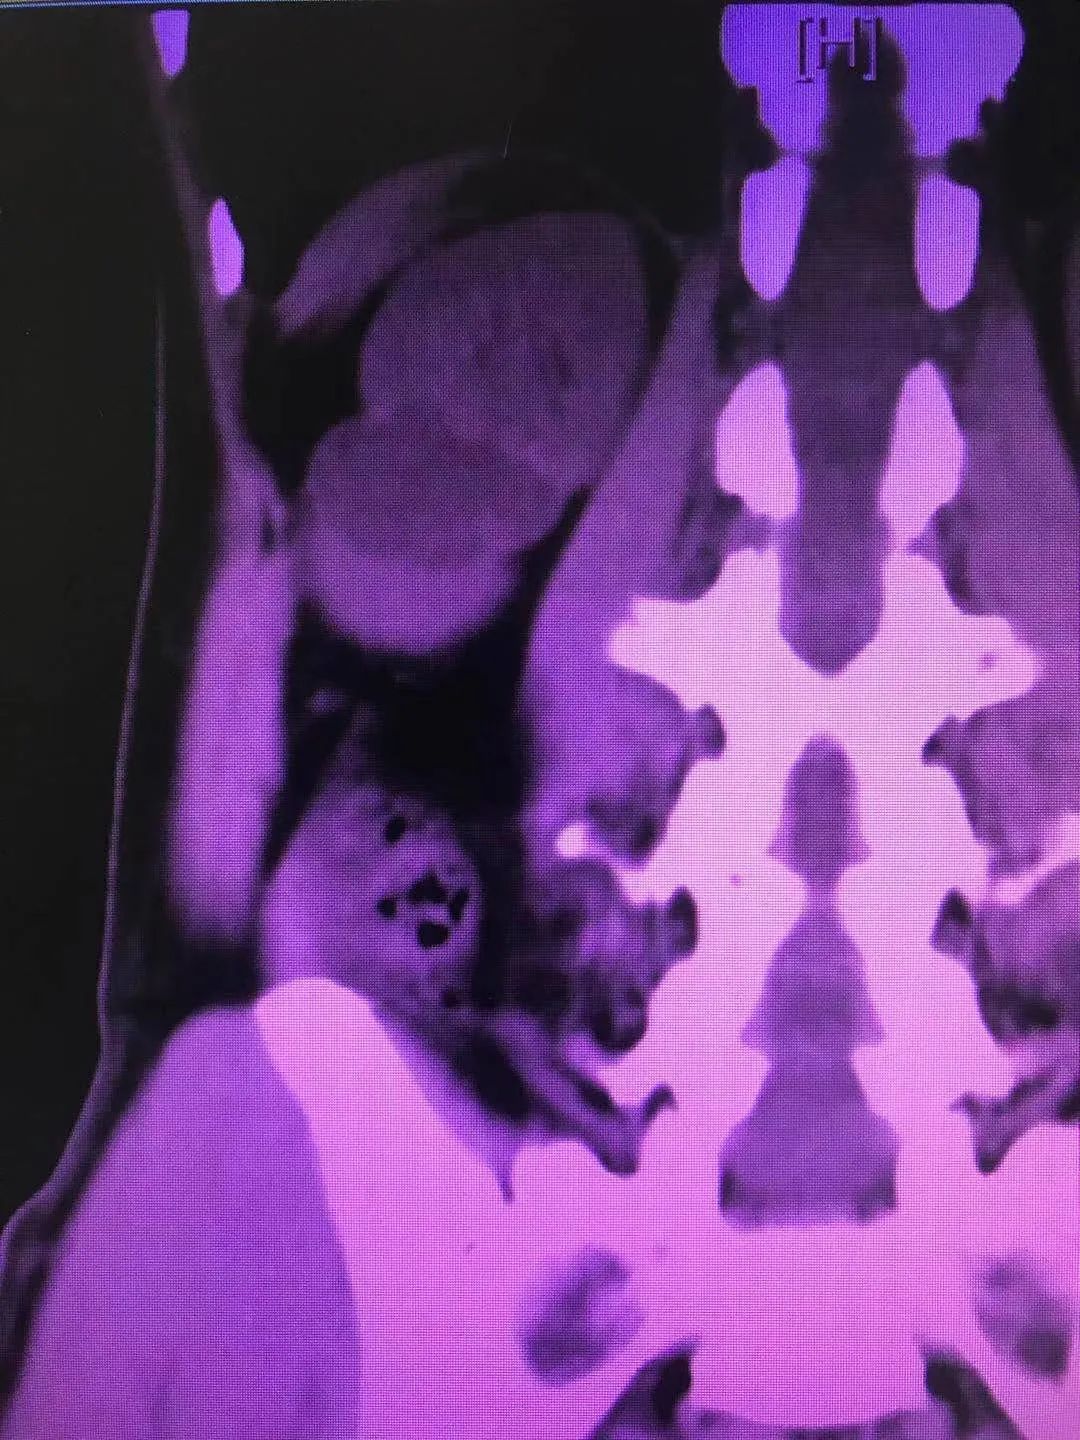

今年1月,医院外一科收治了一名40多岁的男性患者。该患者因腰部绞痛难忍,前来医院就诊。以刘文庭医生和尹曦医生为代表的外一科团队在对病人查体后发现,患者右肾结石散在且多发,结石密度影,肾实质厚,肾囊肿巨大且多发,手术难度颇大。

经过外一科医护团队对患者病情的仔细分析和详细论证,终于设计出一条适合患者病情的风险最小的手术治疗方案,即经皮肾囊肿输尿管软镜下右肾结石钬激光碎石术;利用此技术,将患者复杂性肾结石和肾囊肿通过同一通道经皮肾贯穿囊肿先内引流,再由内引流孔进入肾盂,最后利用钬激光进行碎石。患者利用此新技术前后共进行了两次碎石手术,手术治疗效果良好。第二次碎石手术顺利完成后,患者体内95%的结石碎石成功并成功排除体外,其病情已得到明显好转,目前已康复出院。